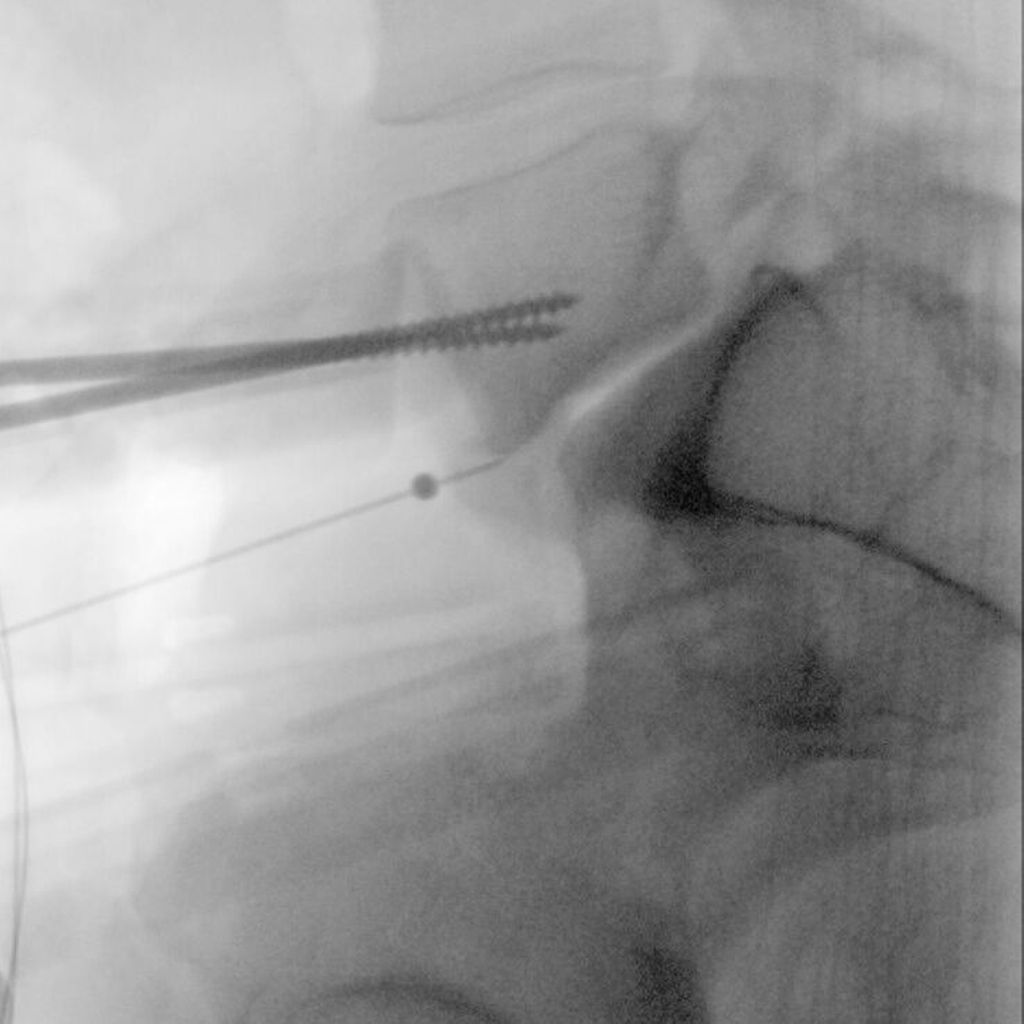

Nach einer medianen Hautinzision bzw. Pfannenstielinzision erfolgt meist ein linksseitiger retroperitonealer Zugang in Rückenlage. Bei einer ventralen multisegmentalen Fusion empfiehlt sich eine paramediane Längsinzision. Nach Darstellen und Inzision der vorderen Rektusscheide sowie Mobilisierung des Muskels wird das Peritoneum stumpf gelöst und mitsamt dem Ureter nach medial präpariert. Danach wird der Bandscheibenraum L5/S1 unterhalb der Gefäßbifurkation dargestellt. Ein Zugang zu den Bandscheibenräumen L4/L5 und darüber erfolgt am medialen Rand des Musculus psoas. Das hintere Blatt der Rektusscheide muss eventuell inzidiert werden. Die Arterie und Vena iliaca communis sowie kranial davon die Vena cava inferior und Aorta abdominalis werden dabei vorsichtig stumpf von lateral nach medial mobilisiert. Bei L4/L5 ist im Besonderen auf eine mögliche Vena iliolumbalis oder Vena lumbalis ascendens zu achten, welche entsprechend ligiert werden sollten. Nach erfolgter Darstellung der vorderen Säule und Einstellen des Situs mit einem in den meisten Fällen selbsthaltenden Retraktorsystem erfolgen das Durchtrennen des vorderen Längsbands und das Ausräumen des Bandscheibenfachs (Abb.1). Anschließend wird der Probecage unter Röntgenkontrolle eingebracht und schließlich das definitive Implantat (Abb. 2). Je nach Implantat kann der Cage mit einem integrierten Schraubensystem in den angrenzenden Wirbelkörpern fixiert werden (Abb. 3, 4).